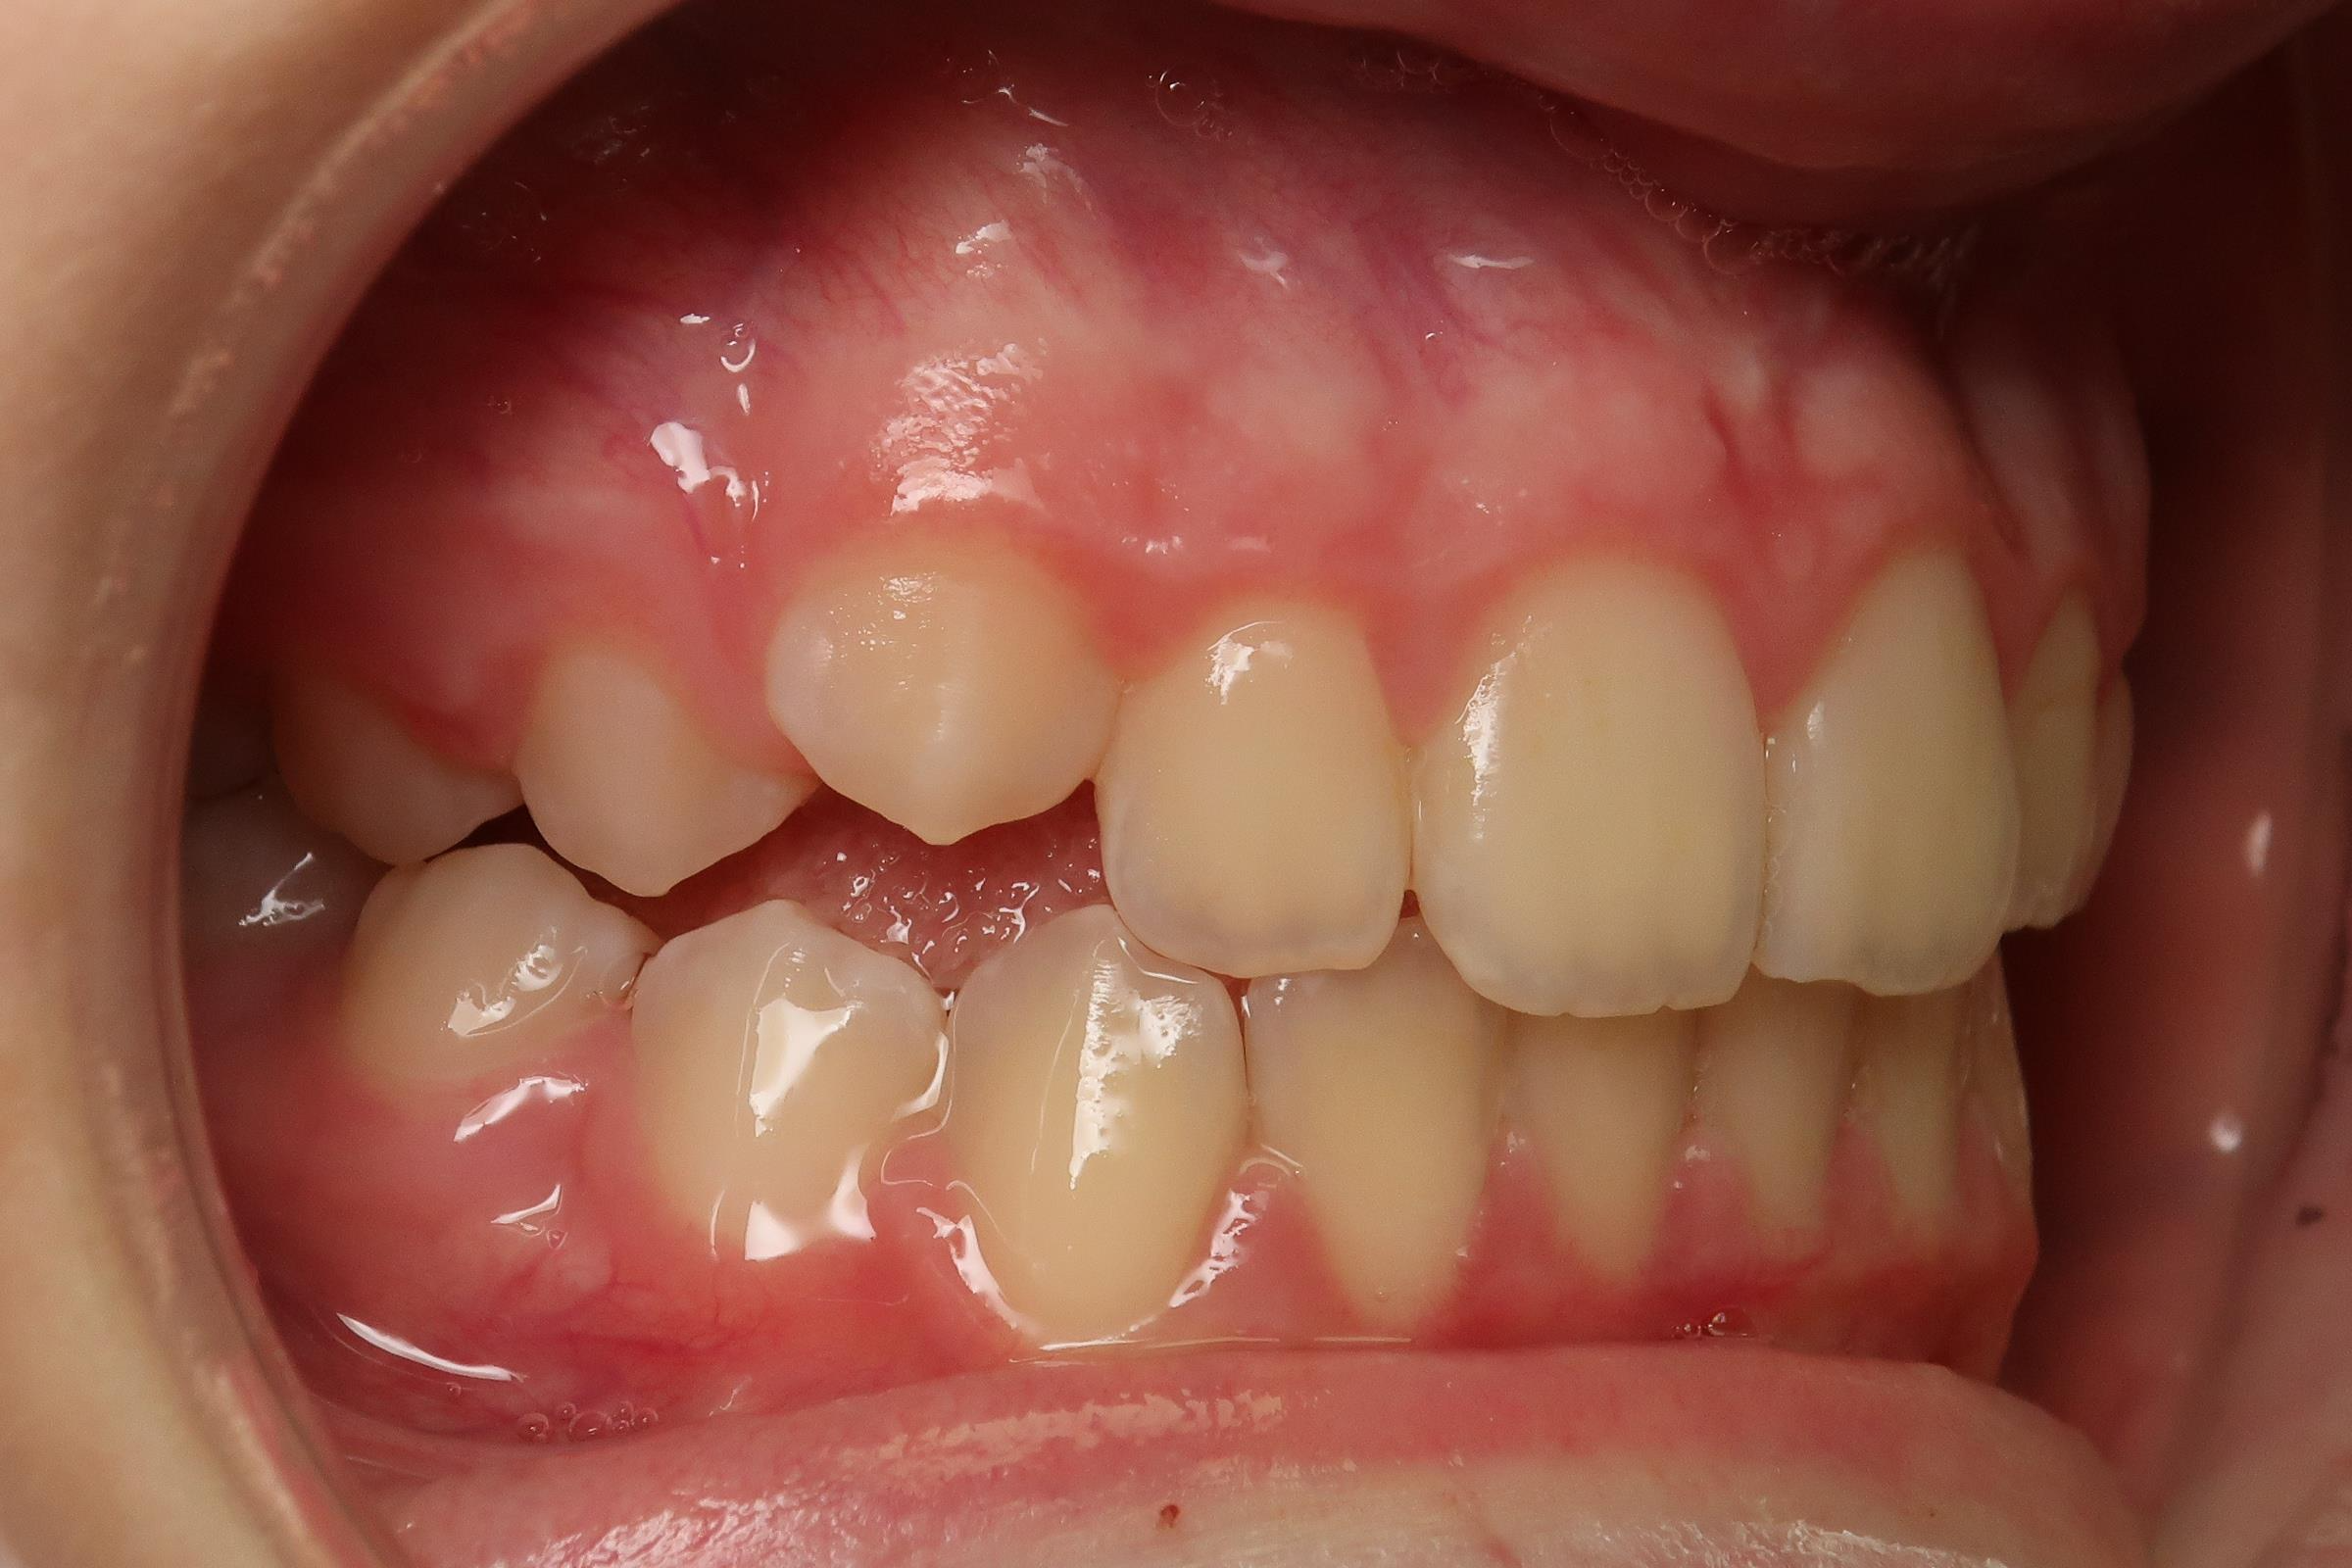

18 béance inversé droit 4 ans

inversion des dents postérieur et espace entre l'arcade du haut et du bas (béance)

appareillage mobile pendant 3 ans

bilan de début et en cours de traitement